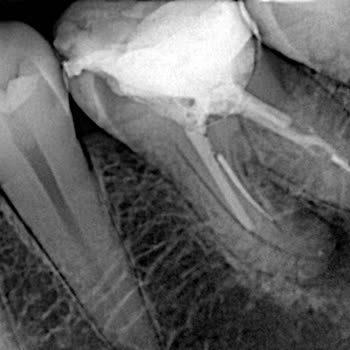

Yenişehir Mahallesi'ndeki Dentreferans Kliniği'ne kanal tedavisi için başvurdum. Tedavinin iki seansta tamamlanacağı söylenmesine rağmen işlem dört seansa çıktı. Üstelik tedavi sırasında dişimde iki adet iğne kırıldı ve kökteki iltihaba ulaşılmadan dişimin üstü kapatıldı. Tedavi tamamlandıktan sonra...